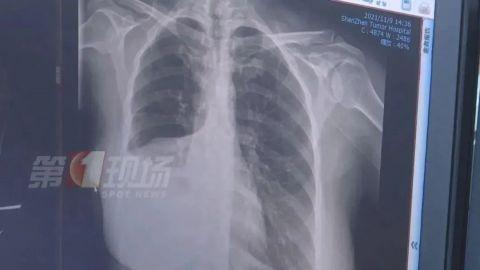

女士做了增强CT后,确实发现肺部有一个五公分左右的肿瘤,医生诊断为肺癌,目前为中期偏早,建议她进行切除手术。